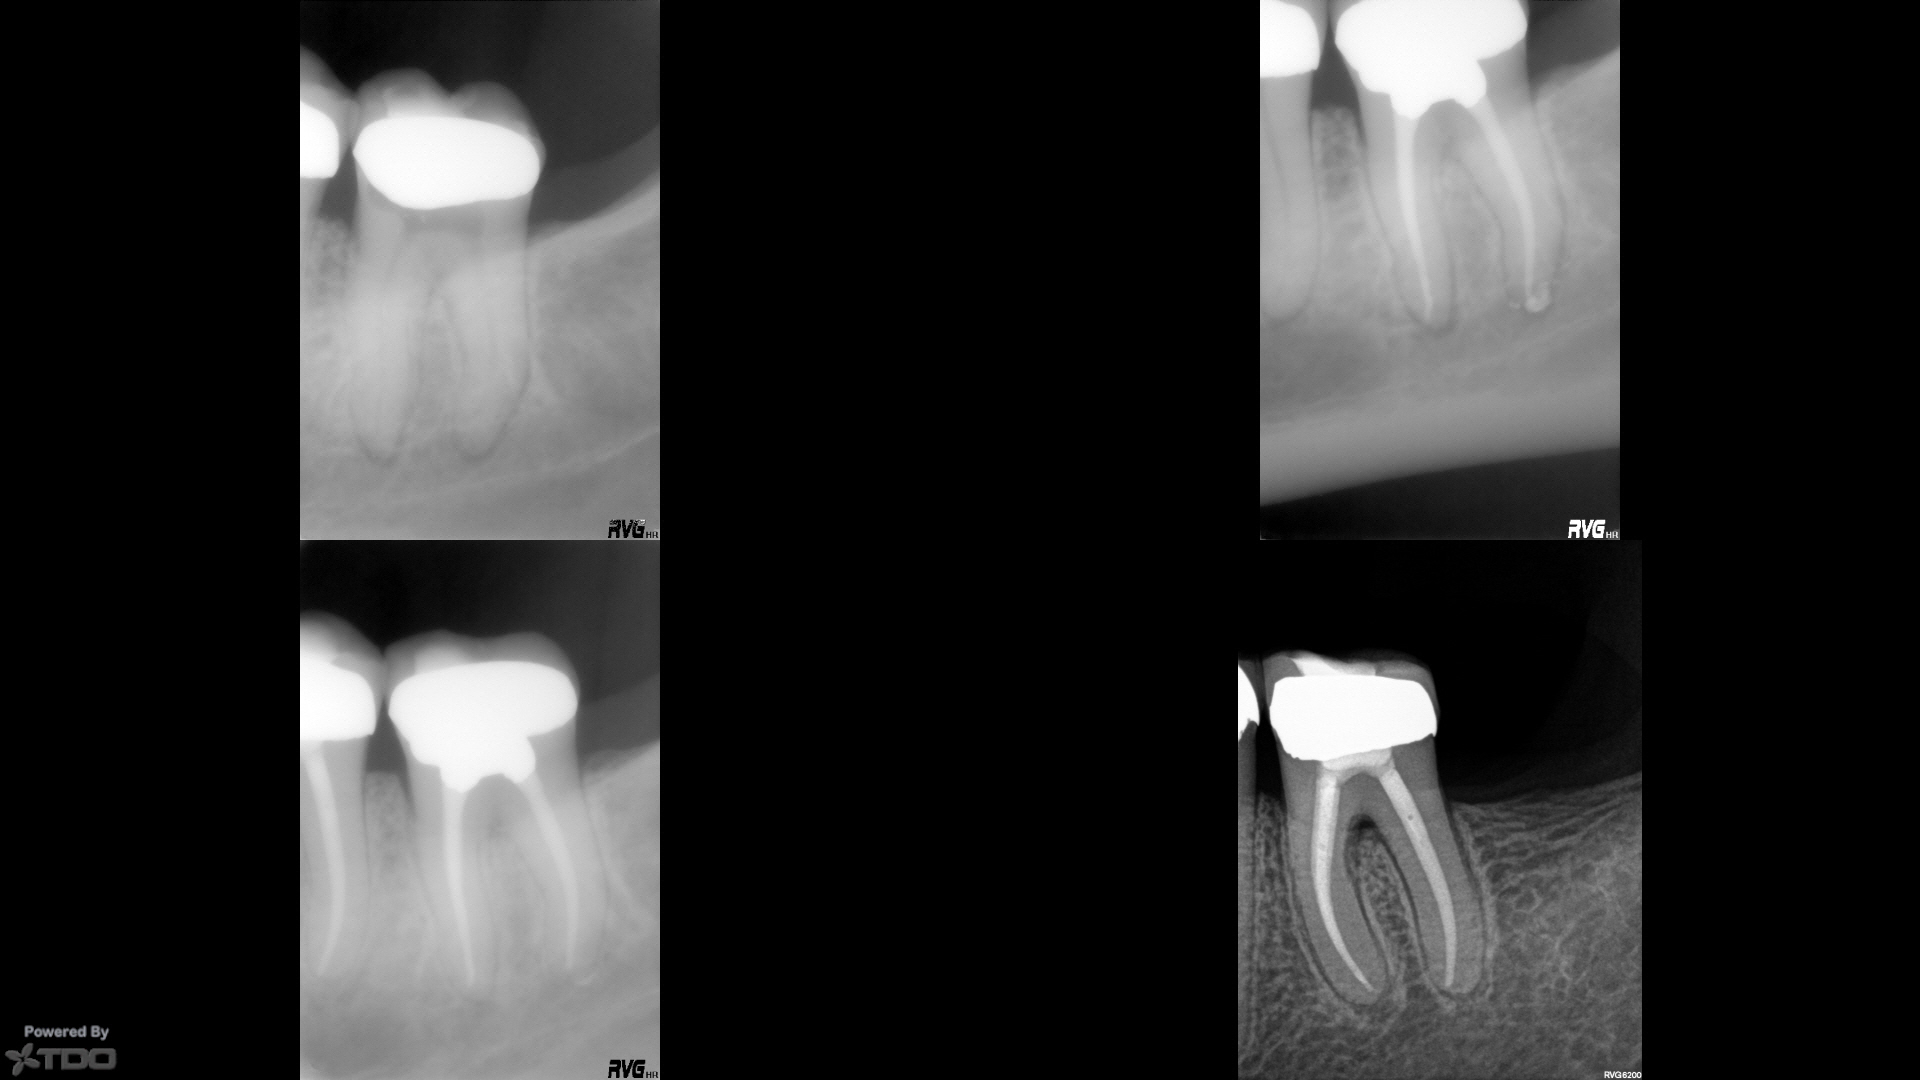

Sent for #13 by one of my best RDs that does partial coverage gold.

I hogged out #18 in 2002 (her clown RD who I fired over a decade ago started it and bashed the access for me), gutted #19 later that year (which was actually the problem tooth), mutilated #14 in 2005, failed to place post in #11 in and I didn't even get to see #15 before it was removed.

#18 is out some years ago, #15 is out for unknown reasons (it was virgin…I'm guessing it split or the clown screwed it up and buried it…which he does), #14 is broken, #19 is still hanging in there, and now #13 is dead.